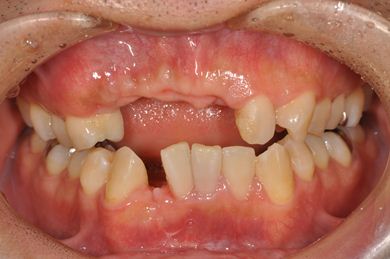

| 性別/年齢 | 男性 / 36歳 | ||||||||||||||||||||||||||||||||

| 主訴 | 事故で欠損した上部の歯4本、下1本のインプラント治療相談。 | ||||||||||||||||||||||||||||||||

| 治療内容 | インプラント2本(GBR、自家骨移植)、メタルボンドセラミック4本、結合組織移植術 | ||||||||||||||||||||||||||||||||